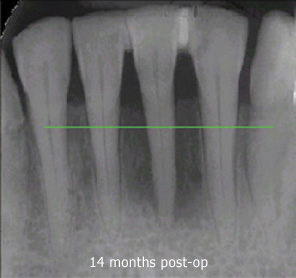

As the gums heal, the teeth will shift, and your bite will need to be adjusted several times over the first few weeks, even for the first year and beyond. Although it seems counter-intuitive, inadequate adjustment is what is usually responsible for soreness or sensitivity following LANAP.

Professional cleaning is recommended every three months for the first year, and re-evaluation of your condition will be done at the twelve month visit. Most people with gum disease remain at risk for the rest of their lives, and would benefit from having their teeth cleaned every three months indefinitely.